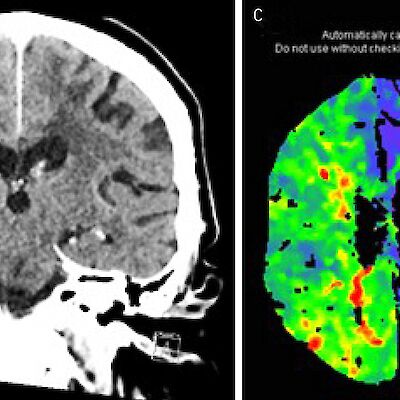

Varhaisen ruutuajan ja ahdistuneisuuden yhteys sai selityksen Keskiössä oli aivojen hermoverkoston kehitys. Nina Kaseva Lääketieteen maailmasta 10.3.2026 Kommentteja